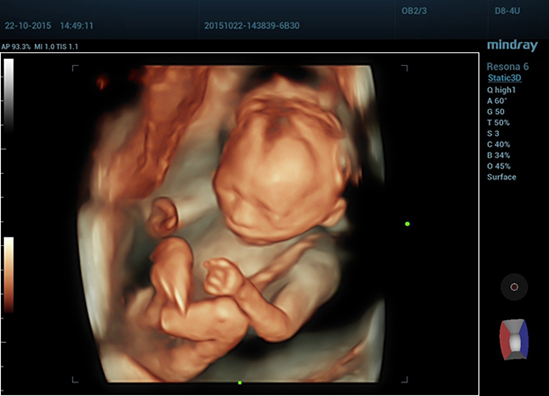

• 07 3D of Fetal Profile

Плод в профиль, трехмерное изображение